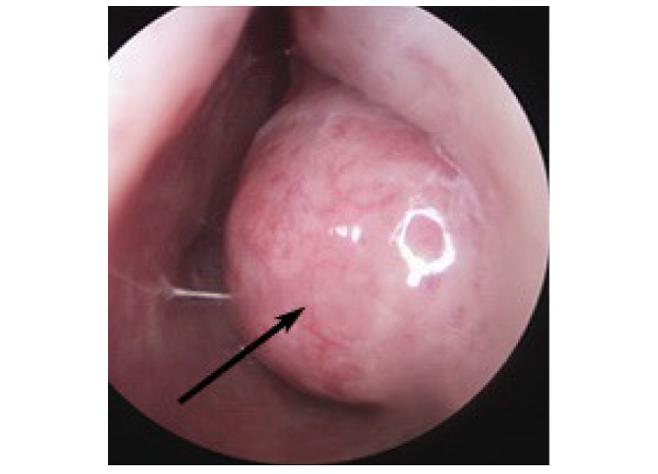

RADIOFREQUENZE IN CASO DI IPERTROFIA DEL PALATO MOLLE

Nei casi in cui il russamento sia dovuto ad aumentato volume e lassità delle mucose del palato molle e dell’ugola, si può perseguire la riduzione del tessuto alterato, (Sclero Riduzione Tissutale non ablativa del palato) inserendo il terminale delle radiofrequenze nello spessore del palato ed erogando energia controllata per 10-15 secondi, in tempi successivi. Si ottiene così la coagulazione e la retrazione cicatriziale del tessuto in eccesso, la riduzione volumetrica del palato e l’irrigidimento del tessuto molle flottante responsabile del russamento. L’intervento viene eseguito in anestesia locale, senza sanguinamento significativo ne dolore significativo per la persona. Il lieve dolore faringeo scompare in 1-2 giorni. Il pieno risultato si esplica dopo circa un mese.

Tuttavia noi riteniamo che mentre sui turbinati ipertrofici l’effetto delle radiofrequenze è molto buono, i risultati della retrazione del palato mediante radiofrequenze non sono soddisfacenti per i pazienti. Questo perché se l’ipertrofia dell’ugola e del palato è lieve, le radiofrequenze sono utili ma la persona in genere non ha motivo di fastidio significativo, se invece l’ipertrofia dell’ugola e del palato è importante, la riduzione con radiofrequenze non è adeguata, e noi preferiamo in questi casi l’uvulopalatoplastica che è grandemente migliorativa.